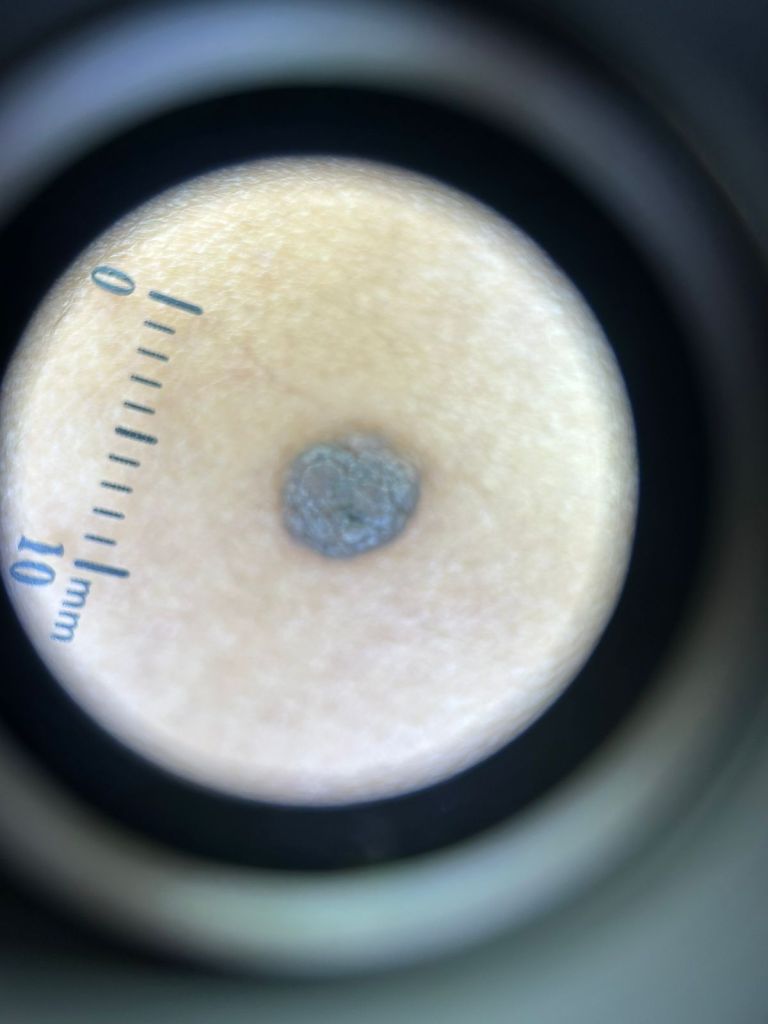

BANDEIRANTES – A Prefeitura Municipal, por meio da Secretaria de Saúde, acaba de incorporar ao seu atendimento um dermatoscópio de última geração, equipamento que representa um avanço importante para a saúde da população. O aparelho possibilita que os profissionais avaliem com maior precisão as lesões de pele, permitindo identificar doenças em estágios iniciais e evitando encaminhamentos ou procedimentos desnecessários.

O dermatoscópio amplia e ilumina a pele de forma não invasiva, revelando detalhes que não são visíveis a olho nu. Estudos apontam que seu uso aumenta significativamente a taxa de diagnóstico precoce de doenças como o melanoma, o tipo mais agressivo de câncer de pele. Essa tecnologia também contribui para reduzir o número de biópsias, tornando o processo de investigação mais ágil, seguro e econômico.